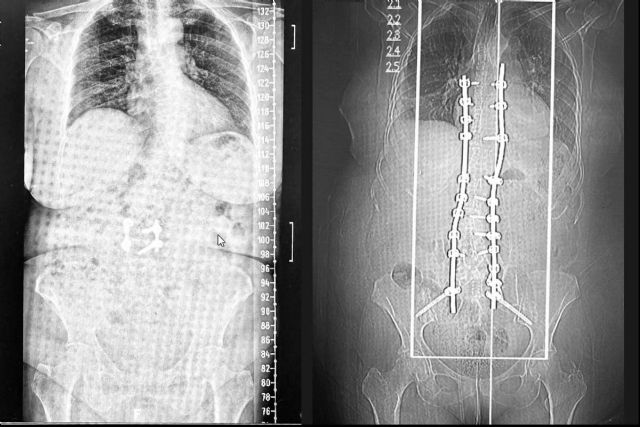

La tecnología de guías 3D permite diseñar dispositivos personalizados que se ajustan a la anatomía única de cada paciente. A partir de estudios de imagen como radiografías, tomografías computarizadas y resonancias magnéticas, se crea un modelo tridimensional de la columna. Este modelo se utiliza para planificar la cirugía y fabricar guías que facilitan la colocación precisa de tornillos pediculares y otros dispositivos de fijación durante la intervención.

Las guías 3D proporcionan una precisión máxima en la colocación de implantes, reduciendo el riesgo de errores y complicaciones. Además, al optimizar la planificación quirúrgica, se disminuye el tiempo de la intervención, la exposición a RX y se favorece una recuperación más rápida del paciente. La seguridad también se incrementa, ya que se minimiza el riesgo de dañar estructuras cercanas como raíces nerviosas o vasos sanguíneos.